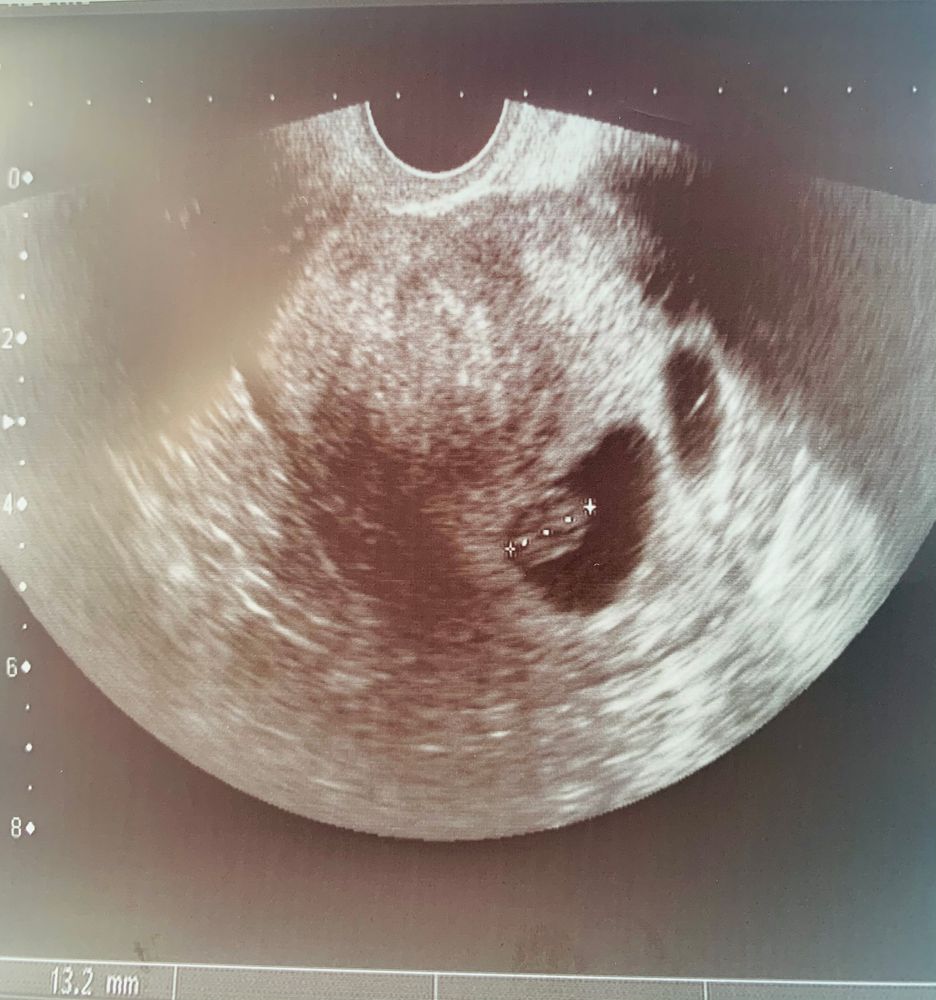

Вот нашла свой снимок, ктр такой же, ну какой тут человек, просто овальчик, человечка я увидела ближе к 9. Главное малыш растёт и развивается, пару дней это такая ерунда Изображение

Да не сильно отстает! У меня когда ктр 13 мм был мне срок по узи поставили 7+5 . Не переживайте! Все хорошо! Малыш ваш красавчик! Догонит и перегонит всех🥰